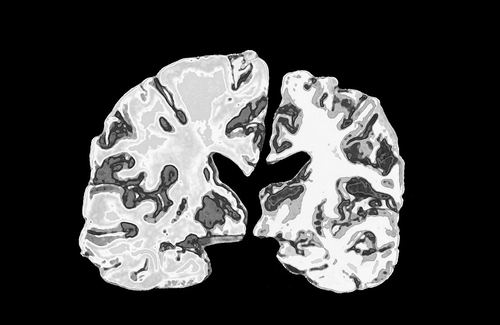

正常人大脑切片(左)与阿尔茨海默病患者大脑切片的对比。图片来源:Jessica Wilson